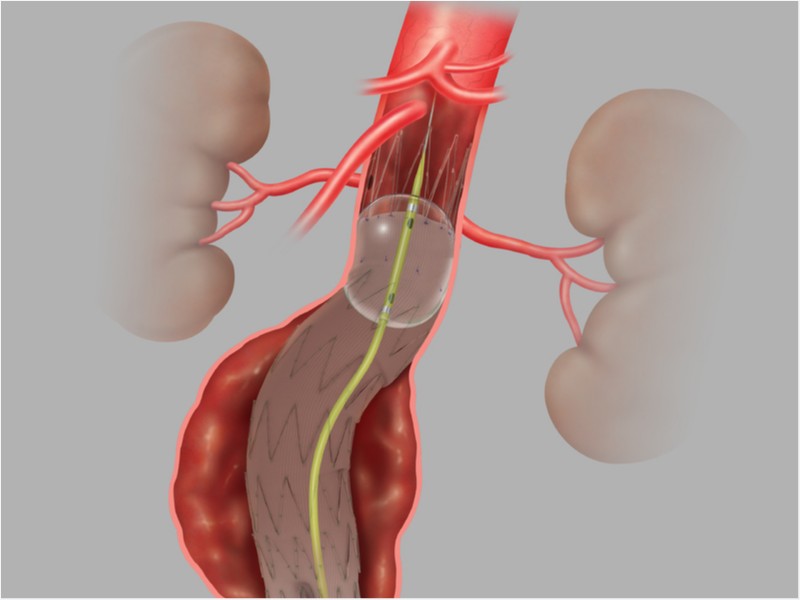

- Endoprótese Endovascular Toracoabdominal Zenith T-BRANCH

Endoprótese Endovascular Toracoabdominal Zenith T-BRANCH

Endoprótese ramificada para aneurisma Toracoabdominal ZENITH® T-BRANCH®, indicada para o tratamento endovascular de pacientes de alto risco com aneurismas Toracoabdominais. Possui Sistema de entrega H&L-B One Shot hidrofílico e aramado de 22Fr.